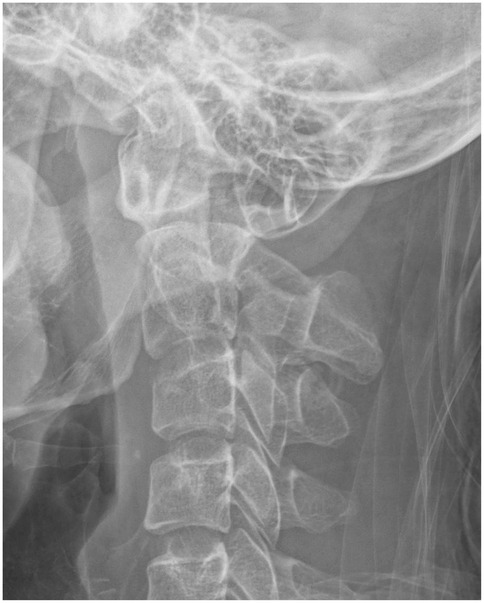

Objective: This retrospective study aimed to analyze the accuracy and safety of pedicle screw placement in upper cervical spine surgery for Hangman's fractures, particularly in cases with high-riding vertebral artery (HRVA) at C2, using navigation technology and 3D-printed patient-specific templates. Methods: We included 33 patients with Hangman's fractures who underwent posterior cervical fixation with bone graft fusion or non-bone graft fusion surgery between January 2013 and January 2023. Patients were divided into two groups based on the intraoperative pedicle screw placement method: Group A (n=15) utilized a navigation system, and Group B (n=18) used a 3D printed navigation template. Clinical and radiological data were collected and compared. Results: One hundred and forty-four screws (66 navigated, 78 3D-printed templates) were inserted without vertebral artery, spinal cord, or nerve injury. Operative time per screw: Group A 24.0±5.6 min vs Group B 18.7±4.1 min; mean difference 5.3 min (22% reduction; 95% CI -9.1 to -1.5; P=0.018). Intra-operative blood loss:152±29 mL vs 105±19 mL; mean difference 47 mL (95% CI -66 to -19; P=0.001). Overall accuracy (Grade 0+1) was 98.5% (65/66) vs 98.7% (77/78) (odds ratio 1.05; 95% CI 0.11-10.2; P=0.97). In the Type-III fracture subgroup (8 screws per group), templates achieved 100% accuracy vs 87.5% with navigation (P=0.032) and lower cortical penetration (12.5% vs 37.5%; P=0.008). Post-operative VAS and NDI improved comparably (all inter-group P>0.05). At 24-month follow-up, all fractures had healed; C2/3 fusion rates did not differ (facet fusion 100% vs 100%; inter-body fusion 39% vs 39%; P>0.99). Conclusion: The use of 3D-printed patient-specific templates in upper cervical spine surgery for Hangman's fractures, especially in the presence of HRVA, is effective and safe. It offers comparable accuracy to navigation-assisted surgery while reducing operative time and blood loss. This approach may be particularly beneficial in minimizing the risk of vertebral artery injury and optimizing surgical outcomes. Compared to navigation technology, it can effectively improve the accuracy of screw placement in extremely unstable fractures.